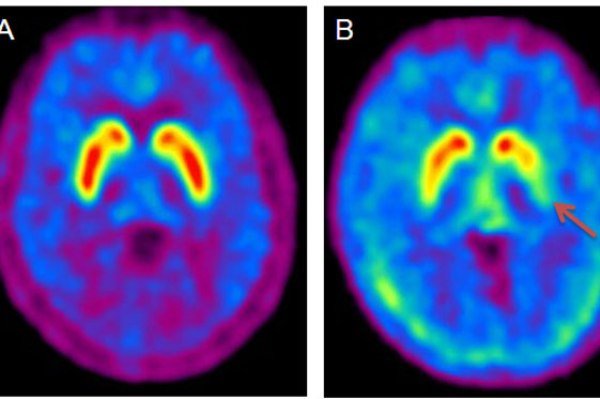

محققان تاثیرات این دارو را با استفاده از مگس سرکه به اثبات رساندند. دریافت داروی UDCA در مگس های سرکه باعث شد تا مسیر پیام رسانی دوپامینرژیک در مگس سرکه ناقل ژن معیوب LRRK۲ تغییر پیدا کند. تغذیه مگس سرکه با این دارو باعث کاهش میزان تحلیل مغز شد.